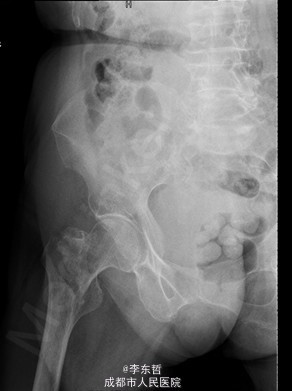

查体:T:37.2oC,P:72次/分,R:18次/分,BP:124/68mmHg。神志清楚,急性病容,皮肤巩膜无黄染,全身浅表淋巴结未见肿大。。颈静脉正常。心界正常,心律齐,各瓣膜区未闻及杂音。胸廓未见异常,双肺叩诊呈清音,双肺呼吸音清,未闻及干湿啰音及胸膜摩擦音。腹部外形正常,全腹柔软,无压痛及反跳痛,腹部未触及包块,肝脏肋下未触及,脾脏肋下未触及,双肾未触及。双下肢无水肿。 专科查体见:右髋关节局部肿胀,周围无红肿、皮肤损伤、溃疡和糜烂,右下肢短缩畸形,无表浅静脉曲张。右转子间轻触痛,扣痛。右髋活动受限,右下肢短缩畸形约5cm,轻度外旋、内收。右髋关节屈伸、外旋内旋、外展内收功能障碍。 X线片示:右股骨转子间骨折,累及大小转子,断端稍分离,未见明显错位,周围软组织肿胀明显,右髋关节在位。

初步诊断:1、右股骨转子间骨折(Evans III型);2、骨质疏松症。 诊疗计划:1、向患者及家属交待病情及注意事项。2、向上级医生汇报患者病情。3、完善术前相关检查。4、给予皮肤牵引、抬高患肢等对症处理。5、拟手术治疗。6、密切观察病情变化,根据病情及时处理。